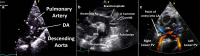

Cardiac ultrasound techniques are increasingly used in the neonatal intensive care unit to guide cardiorespiratory care of the sick newborn. This is the first in a series of eight review articles discussing the current status of "neonatologist-performed echocardiography" (NPE). The aim of this introductory review is to discuss four key elements of NPE. Indications for scanning are summarized to give the neonatologist with echocardiography skills a clear scope of practice. The fundamental physics of ultrasound are explained to allow for image optimization and avoid erroneous conclusions from artifacts. To ensure patient safety during echocardiography recommendations are given to prevent cardiorespiratory instability, hypothermia, infection, and skin lesions. A structured approach to echocardiography, with the same standard views acquired in the same sequence at each scan, is suggested in order to ensure that the neonatologist confirms normal structural anatomy or acquires the necessary images for a pediatric cardiologist to do so when reviewing the scan.